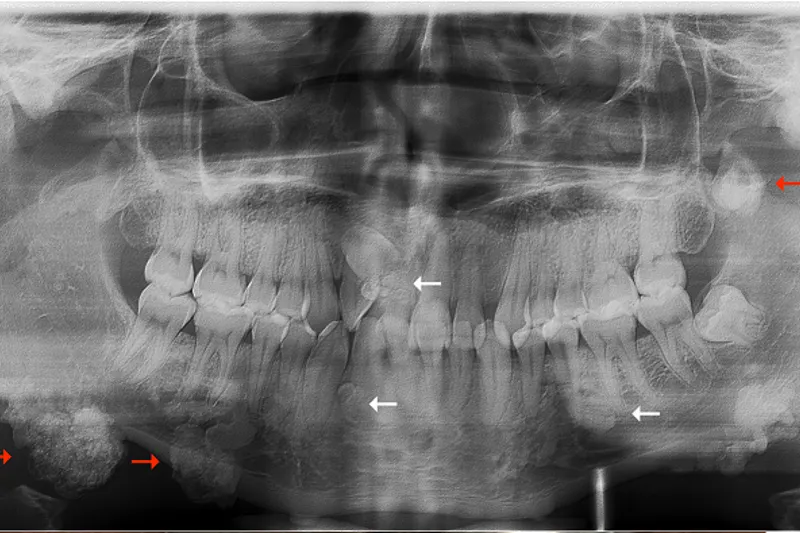

BAGGRUND – Familiær adenomatøs polypose er en sjældent forekommende arvelig tarmsygdom, som er karakteriseret ved udvikling af fra 100 til flere tusinde kolorektale polypper og ekstrakoloniske manifestationer, herunder osteomer i kæberne og tandanomalier.

PATIENTTILFÆLDE – En 29-årig mand blev henvist fra sin privatpraktiserende læge til Kæbekirurgisk Afdeling, Aalborg Universitetshospital, med henblik på diagnostik og behandling af let symptomgivende og kosmetisk skæmmende langsomt voksende hårde hævelser bilateralt langs basis mandibulae.

Patienten var kendt med familiær adenomatøs polypose.

Histologisk undersøgelse af excisionsbiopsier viste forandringer forenelige med osteomer som led i familiær adenomatøs polypose.